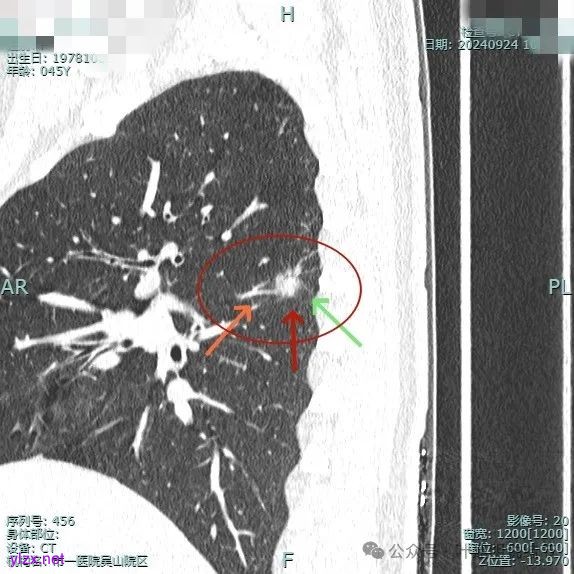

病灶2:

右中叶内侧段可见混合密度结节,大部分实性,形态与下叶背段的类似。

病灶1:

病灶是混合密度,边缘少许淡磨玻璃,灶内不太致密,表面不平,血管征有,但说不上明显异常增粗。

病灶紧贴叶间裂,而且感觉跨过肺叶,部分影响到上叶了,病灶本身密度虽实性为主,但是不太致密,有点松散的感觉。

总体实性部分密度较高,而磨玻璃部分密度较低,且瘤肺边界欠清,关键是跨叶间裂生长,这与肿瘤似乎不容易解释些。

毛刺有但不太锐利,磨玻璃有但偏淡,实性为但不太致密,叶间裂与之关系密切,病灶跨叶生长。

上图显得与肿瘤较为符合,但跨叶生长的话,侵袭力应该较强,可她这病灶较刚发现时进展并不太明显。

上图层面也较符合恶性,血管进入明显,有浅分叶的样子,整体觉得有一定收缩力与膨胀感。

病灶表面不平,混合密度,磨玻璃成分较淡。